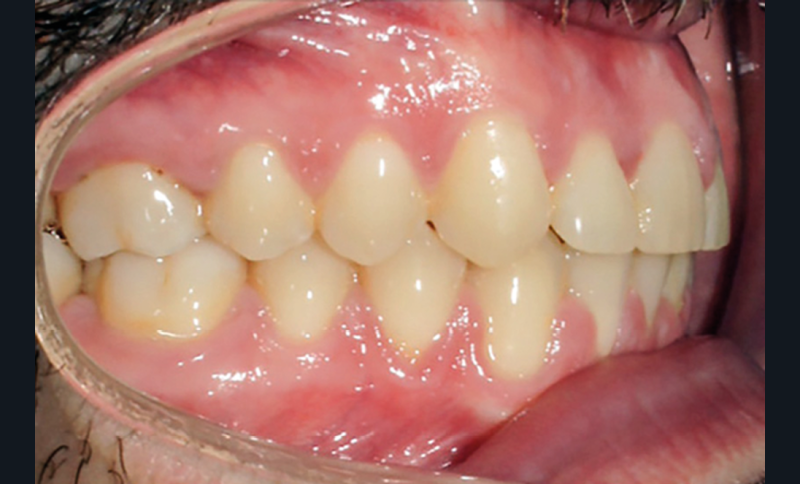

Discussion (fig. 4 à 7)

Le traitement a duré vingt-quatre mois. Le décalage de classe II complet à droite a nécessité une mécanique importante impliquant une bonne coopération du patient ainsi qu’un contrôle rigoureux des effets parasites. Les documents de fin de traitement nous montrent une normalisation des rapports incisifs. La correction de la classe II a entraîné une vestibulo-version de l’incisive mandibulaire qui reste néanmoins acceptable, et qui participe à la fermeture de l’angle interincisif, recherchée dans le traitement des classes II division 2. Les fonctions ont été rééduquées. Sur le plan esthétique, les améloplasties réalisées sur les bords libres de 12 à 22 ont permis d’effacer les séquelles de la supraclusion et participent à l’harmonisation du sourire.